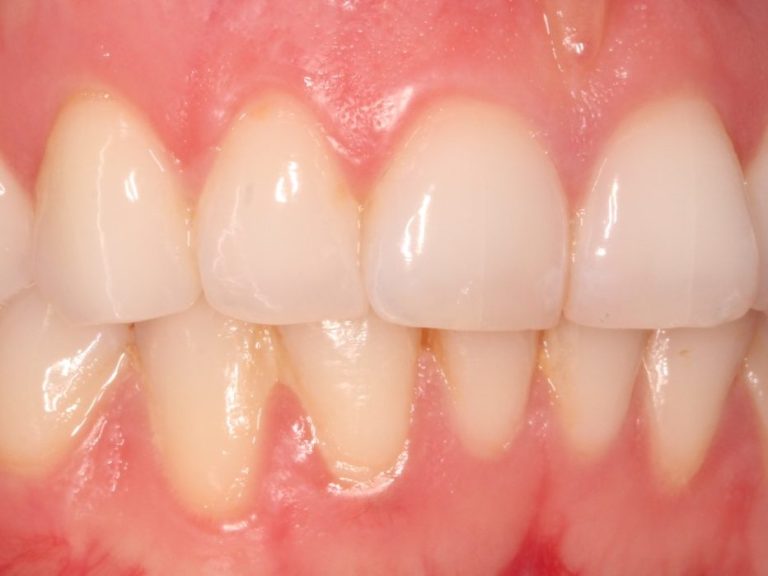

Chirurgie parodontale

Pour traiter les parodontites avancées (infections des gencives et de l’os):

Lambeaux parodontaux (nettoyage en profondeur sous la gencive)

Greffes de gencive pour recouvrir une racine exposée